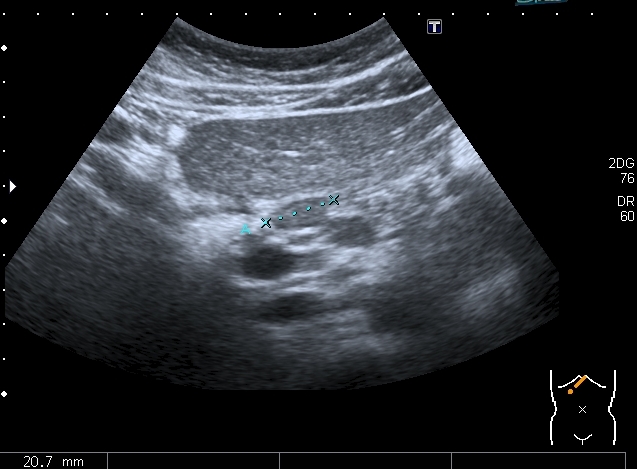

Девочка 13 лет, в течение 2-х недель температура до 38, СОЭ - 40 мм\ч, СРБ - 30.

На УЗИ: Учитывая клинику, лабораторные данные поставил гистиоцитарную инфильтрацию печени и селезёнки при генерализованной инфекции. Несколько раз встречался со схожими случаями, на фоне антибиотикотерапии изменения уходили. Но в данном случае девочка уже получала антибиотики в течение недели, на этом фоне не получено ни клинического , ни лабораторного улучшения, а на УЗИ очаги стали больше. Нужно ли расширять дифференциально -диагностический ряд? Ваши мнения

Имхо, по УЗ-семиотике - множественные небольшие абсцессы.

Из -за того , как назвать данные изменения у нас в больнице постоянно возникают споры между педиатрами и хирургами, а крайние - мы. Если мы в своём заключении упомянём слово "абсцесс" - девочку сразу же переведут в хирургическое отделение: абсцесс= гной, где гной - там разрез. Весь вопрос в том , что гноя в этих очагах нет и хирурги категорически отказываются участвовать в лечении данного заболевания, скорее это инфильтраты, или по лекции С. И. Пиманова - гистиоцитоз печени и селезёнки. Упомянув данное слово , мы ввергаем педиатров в панику, т. к. у них возникает ассоциация с гистиоцитозом X, хотя это несолько из другой оперы.KapustinSV писал(а):Имхо, по УЗ-семиотике - множественные небольшие абсцессы.

Что касается пункции - ИМХО ТАБ в данном случае не даст адекватного диагностического материала для цитологии , кроме того данная процедура инвазивная и у детей проводится под наркозом.

Есть мысль о КТ с контрастированием , думаю в данных очагах накопление контраста должно отличаться от очаговых поражениях при лимфомах.